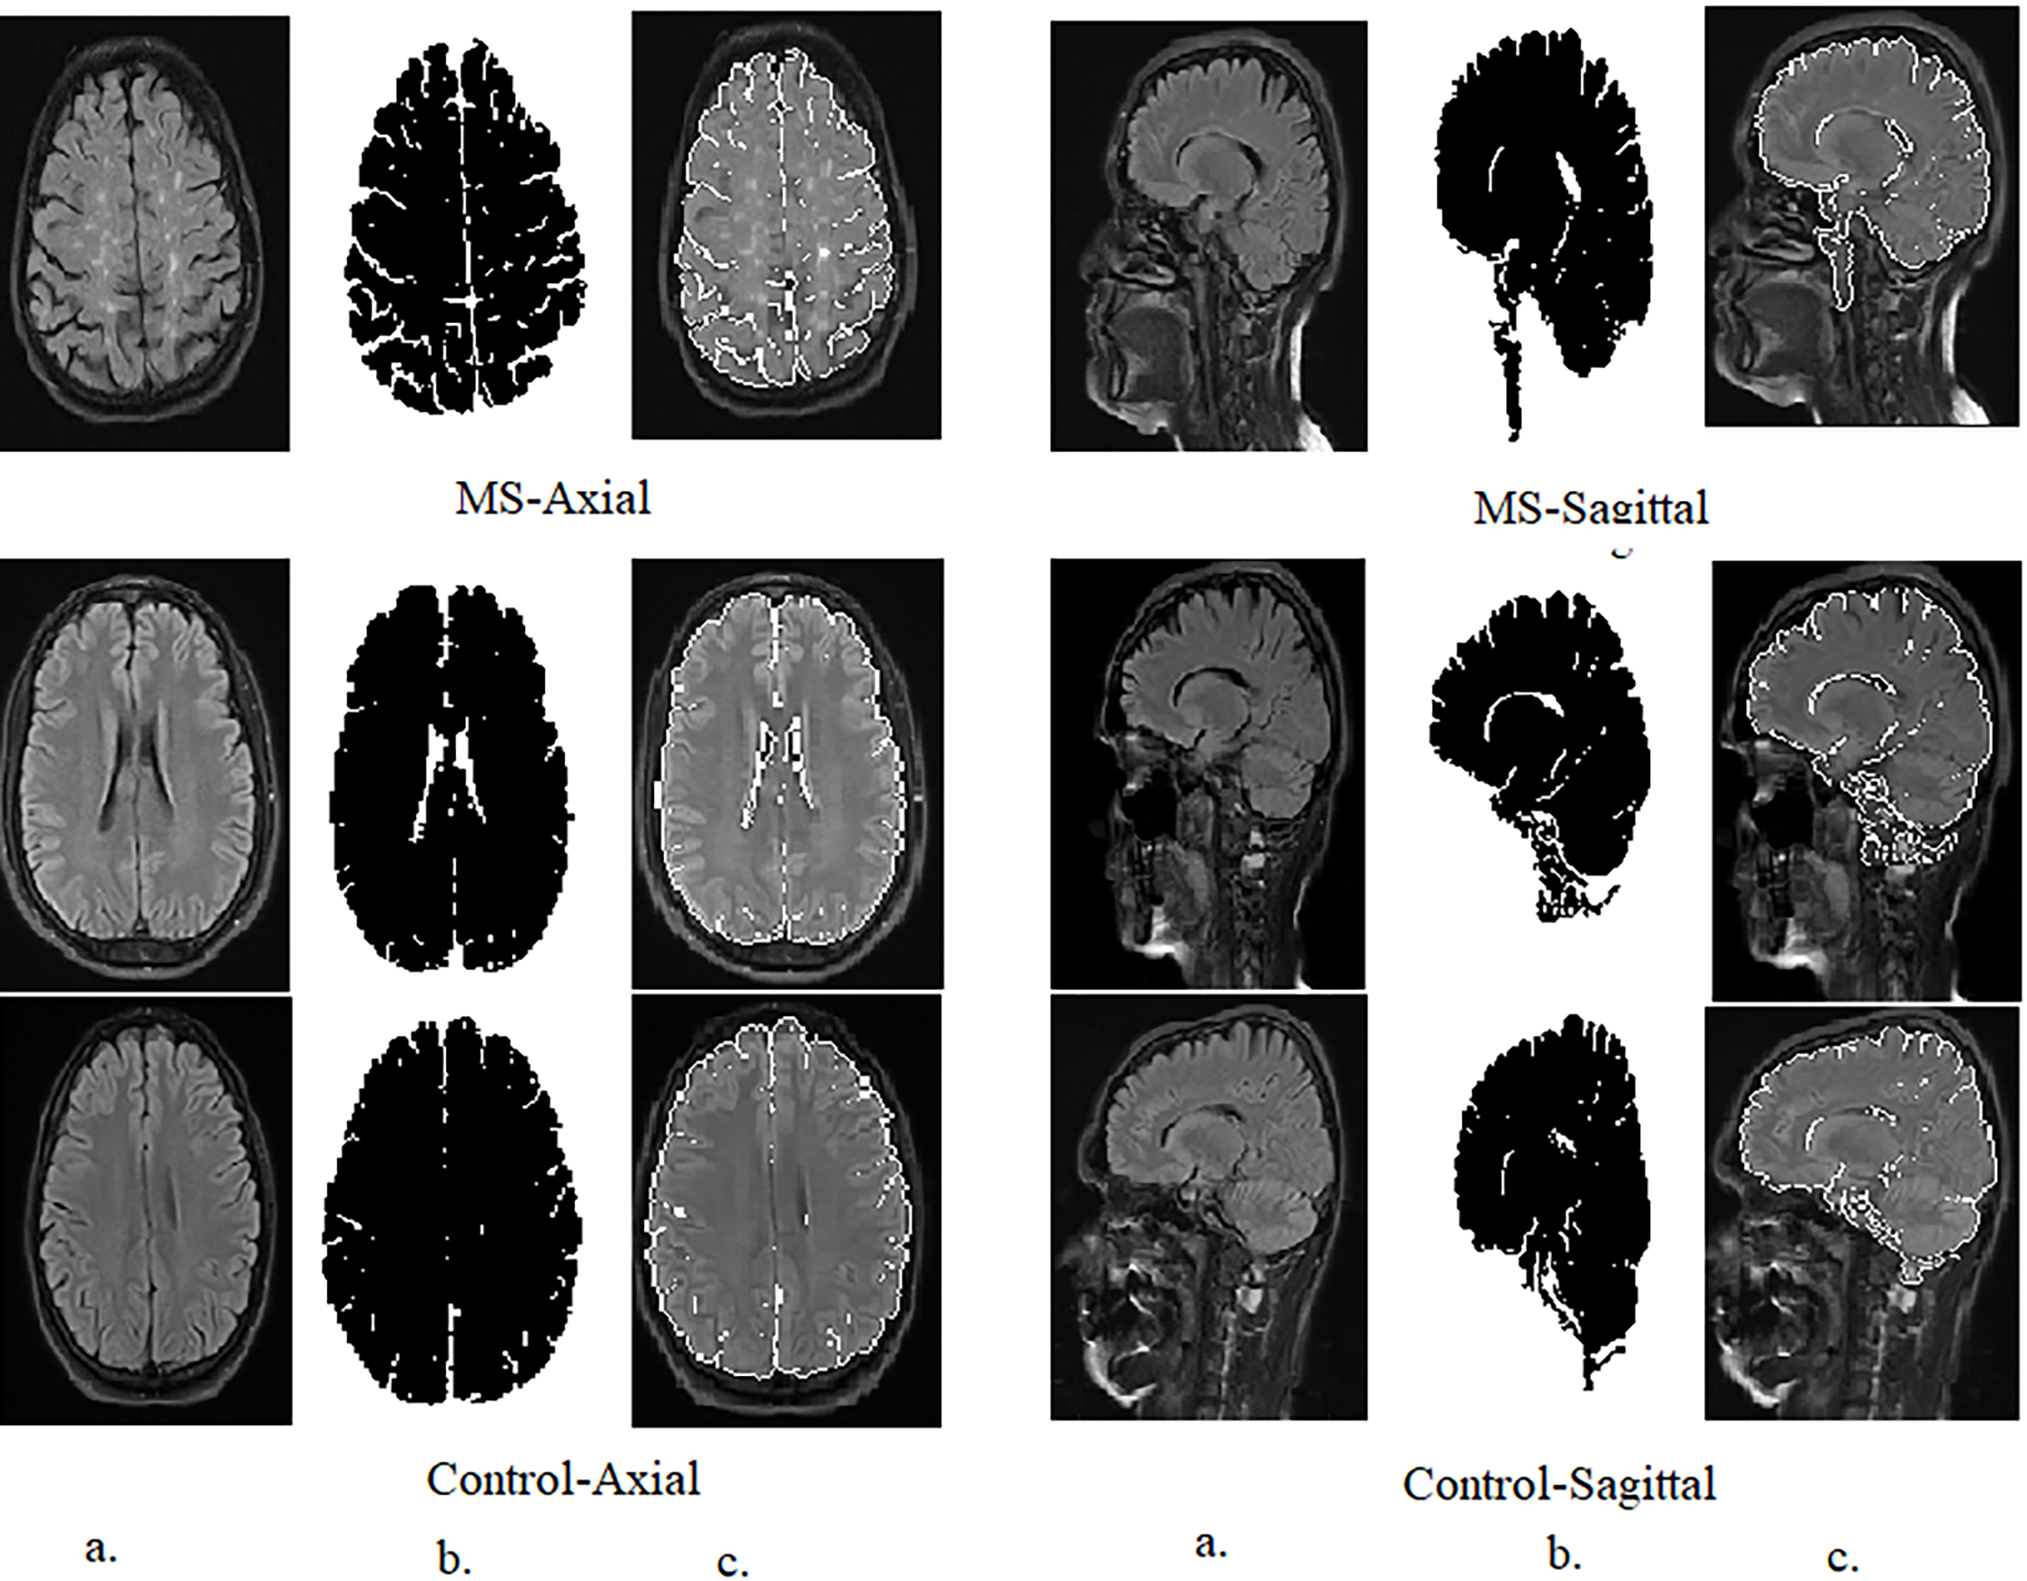

This study uses a dataset of brain MRI images containing confirmed cases of MS and healthy subjects obtained from a trusted public research data repository, Kaggle; the aim is to facilitate the development and evaluation of automated diagnostic methods for early MS screening. The dataset comprises 3427 total axial and sagittal MRI images optimized for visualizing white matter lesions indicative of MS. Cases include 1411 MRI images across MS patients, divided into 650 axial images and 761 sagittal images showing disease manifestations. Controls healthy include 1002 healthy axial images and 1014 healthy sagittal images [30]. This standardized collection allows binary-class evaluation to distinguish MS from healthy states and multi-class analysis of axial and sagittal differences in MS lesions and healthy images. Sample images depicting representative MRI findings in MS are provided in Fig. 2a to illustrate the diversity of scans available for system development and evaluation on this curated data source toward advancing automated multi-orientation MRI analysis methods for early assistance in MS classification.

Figure 2: Samples of the MS dataset randomly selected from an MRI image. (a): Before pre-processing; (b): After pre-processing

Recombining the transformed tiles to form the final CLAHE-enhanced image. Combining processed tiles to reconstruct the entire image. The adaptive nature of CLAHE allows it to focus on local details, enhancing contrast where needed while preserving the overall structure of the image [32]. This makes CLAHE particularly effective at improving the visibility of structures in low-illumination regions of MRI images, making it valuable for applications such as the MS dataset, where accurate and clear imaging is critical for classification. As shown in Fig. 2b, the randomly selected samples show the results of MRI image enhancement.

The contour evolves until convergence is reached, indicating that the contour has stabilized around the border of the brain’s white matter lesion area. The final segmented contour defines a mask that isolates the white matter region of the brain [36]. Fig. 3 shows random samples from the axial and sagittal MS dataset after using the GVF algorithm for segmentation.

Figure 3: Samples from the axial and sagittal MS dataset after segmentation and ROI (Region of interest) identification. (a): Original images; (b): Segmented image; (c): Select the region of interest

These parameters were carefully chosen to ensure that the GVF algorithm effectively isolates the hyperintense areas within MS lesions, which are often sufficient for accurate classification by the CNN models used in this study, as Table 2. The goal was to identify the diagnostically relevant parts of the lesions, even if the entire lesion is not segmented, as these hyperintense regions can provide enough information for accurate MS detection.

The intention behind using GVF was to focus on the most hyperintense areas or edges within the MS lesions, which are often sufficient for classification. It is true that in some cases, not the entire lesion is segmented. However, the aim was to identify the most diagnostically relevant parts of the lesions, as even small portions of hyperintense areas can provide enough information for the CNNs to accurately detect MS.

In Fig. 3, the segmented images are used as input to the CNNs. The process of selecting the ROI was as follows: After applying GVF for segmentation, the white matter lesions were isolated from the surrounding brain tissue. This segmented area, containing the lesions, was then designated as the ROI. The ROI is essentially the area of the image where MS-related features are most prominent, ensuring that the CNNs focus on the most relevant parts of the image.